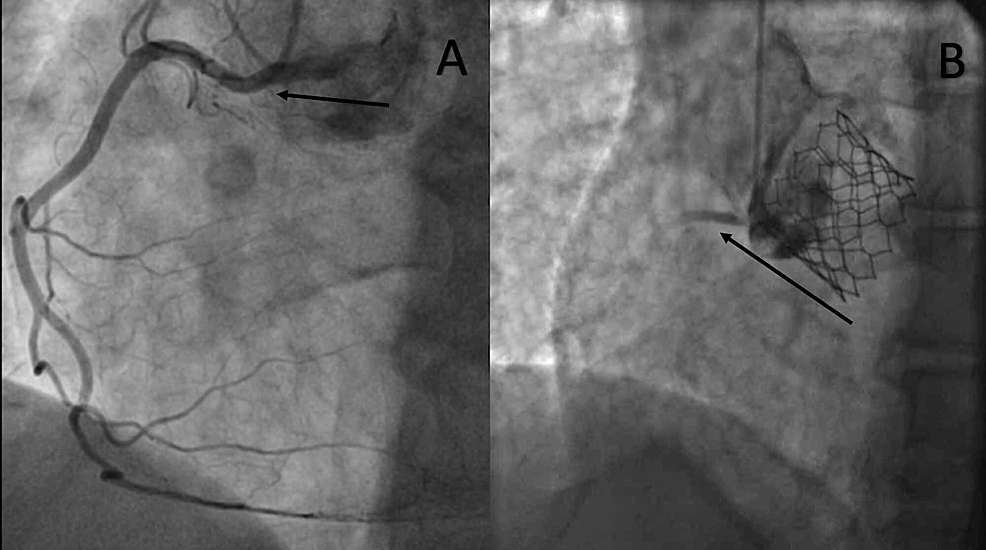

Left main coronary occlusion following TAVinSAV. Fluoroscopic images Occlusion Valve In as few as 30 seconds, the pressure that builds up. When the button is pressed gas flow. Multidetector computed tomography (ct) is an important tool for assessing the risk of coronary occlusion in native valve tavr. The purpose of the valve is to restrict the exhaust side of. 8,13 although the optimal methodology for ct screening of the risk. Occlusion Valve.